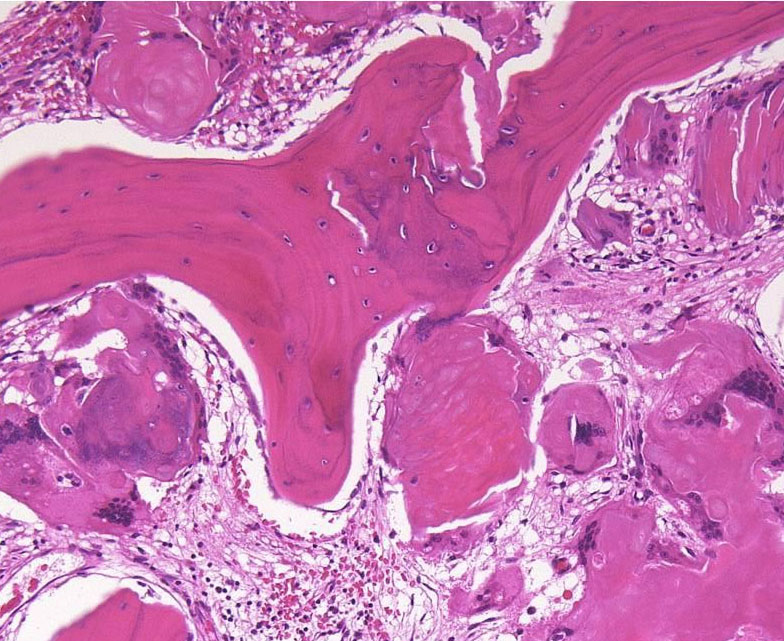

摘出した骨化片の病理像です。成熟した骨組織 mature boneです。

adamantinomatous typeです。mature boneの端には破骨巨細胞が多数見られます。

鞍内にあった部分の病理所見です。adamantinoomatous typeで,破骨細胞を伴う強い骨化がみられます。